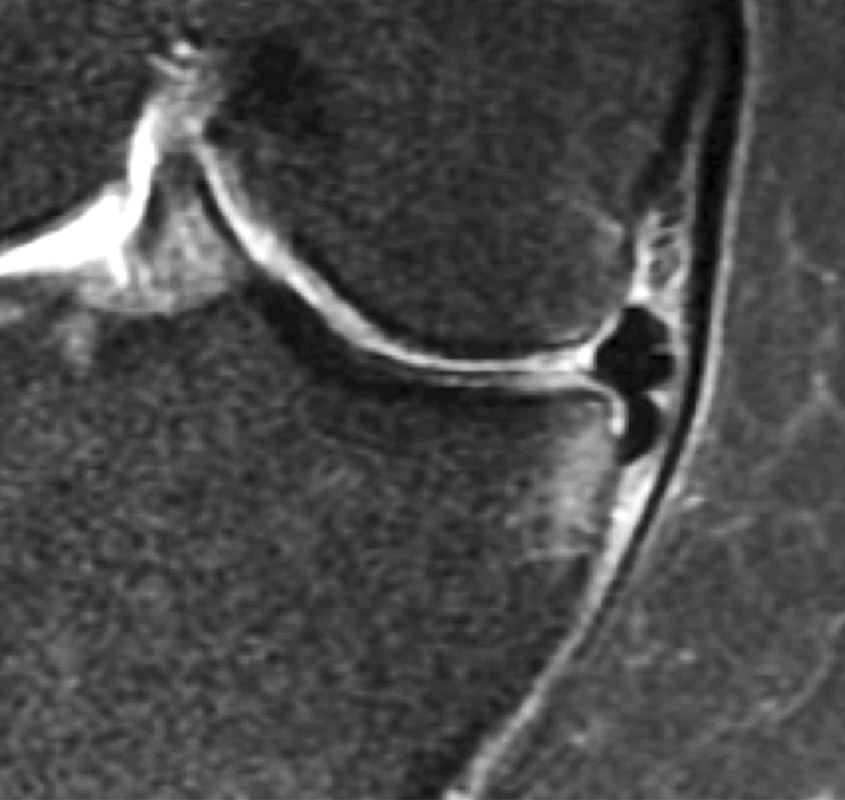

La indicación de una MPA precoz debe estar en función de la intensidad y la frecuencia de los síntomas mecánicos, así como de un completo reconocimiento físico (Figura 5) (grado D).

Figura 5. Fragmento del menisco interno subluxado en la gotera tibial con pinzamiento óseo. Este tipo de lesión degenerativa específica del menisco podría dar lugar a importantes síntomas mecánicos y dolor.